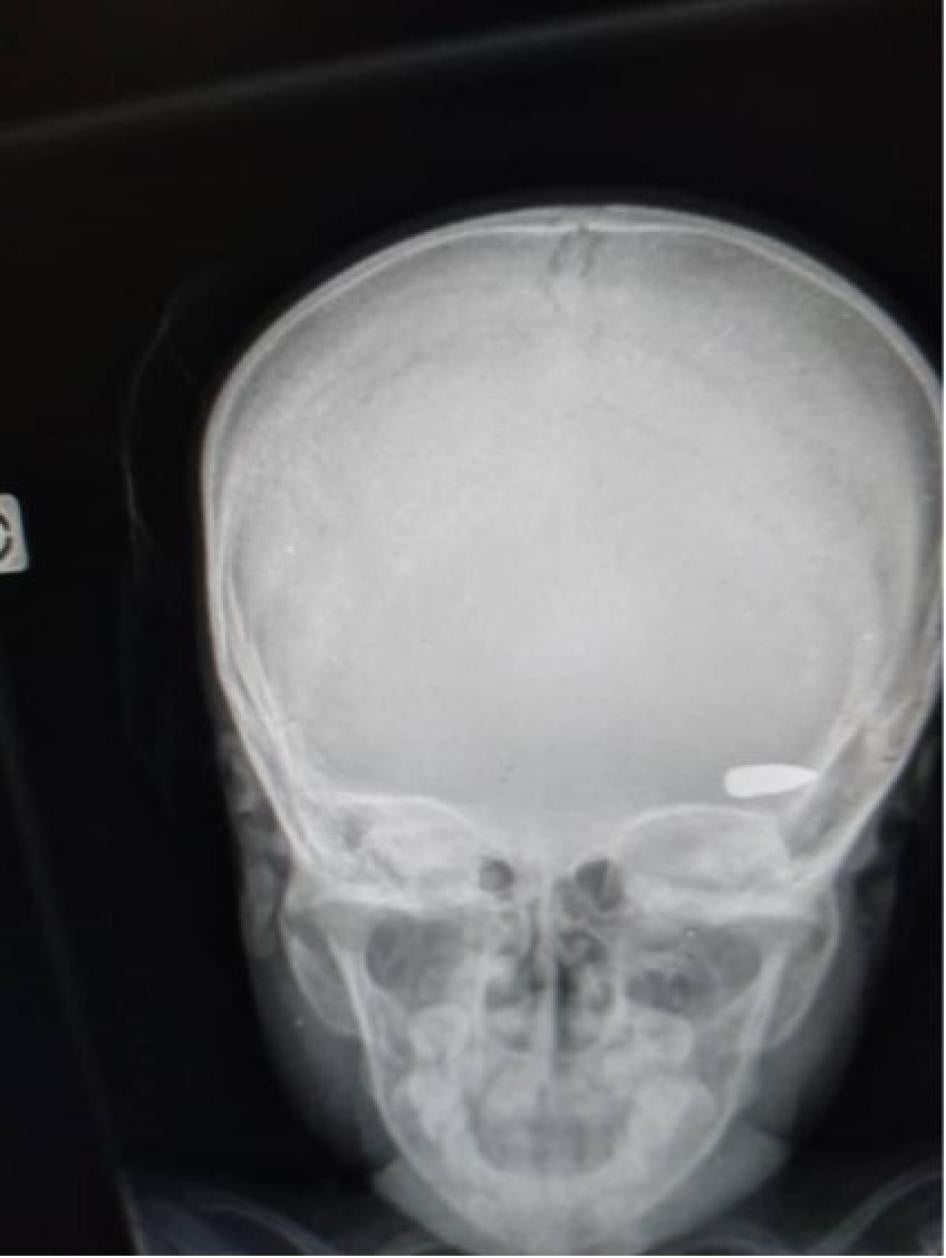

Yon imaj radyografi ki montre bal nan tèt yon timoun ki viktim pandan afwontman ant gwoup kriminèl nan katye Brooklyn nan komin Site Solèy nan kòmansman Avril 2023. © 2023 Prive